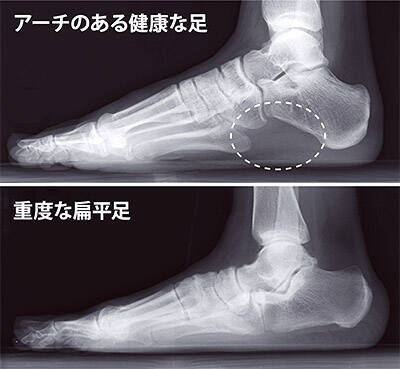

土踏まず が ない 人 土踏まずがないとどんな影響がある 土踏まずを作る方法は 補正ハイカットシューズ 足底板対応靴 装具対応靴ならサスウォークのサスプランニング For more information and 土踏まずがない。「自分はこれが普通だと思っていたら、他の人と足の形が違う。」 気づいたときには、扁平足になっていて、原因もわからない。 こんな風に、諦めかけていませんか? でも、実は、扁平足は約9割が生活習慣によるもので、正しい手順でケアを行えば改善することも可能な 扁平足の原因は? こんにちは。 足立区竹の塚にあるわしざわ整形外科スポーツ整形外科リハビリテーション科、理学療法士の遠藤です。 今回は、扁平足について説明したいと思います。 人の足は本来、横から見ると 土踏まずに沿って弓のよう

扁平足の原因は わしざわ整形外科 新着ニュース